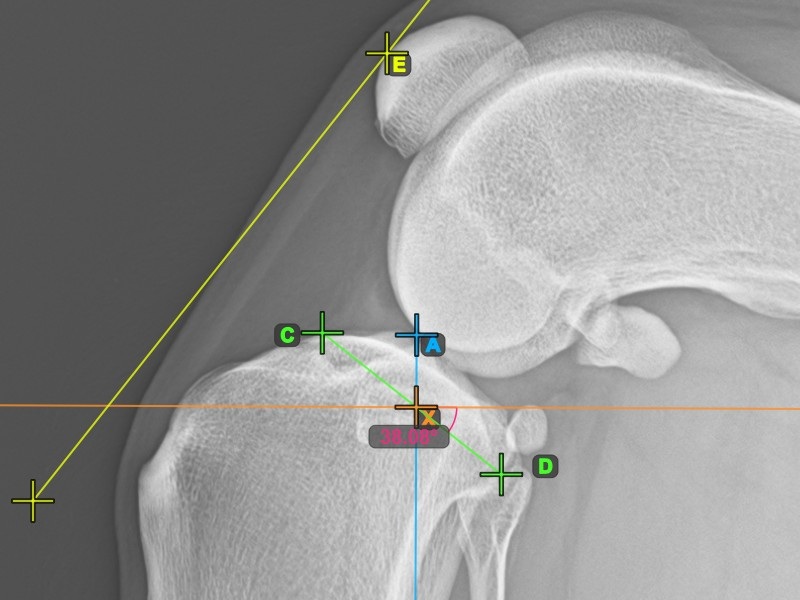

A lenti kép a tibia plató legalacsonyabb pontjának szokásos elhelyezkedését és az automatikusan kiszámított TPA szög mérését ábrázolja.